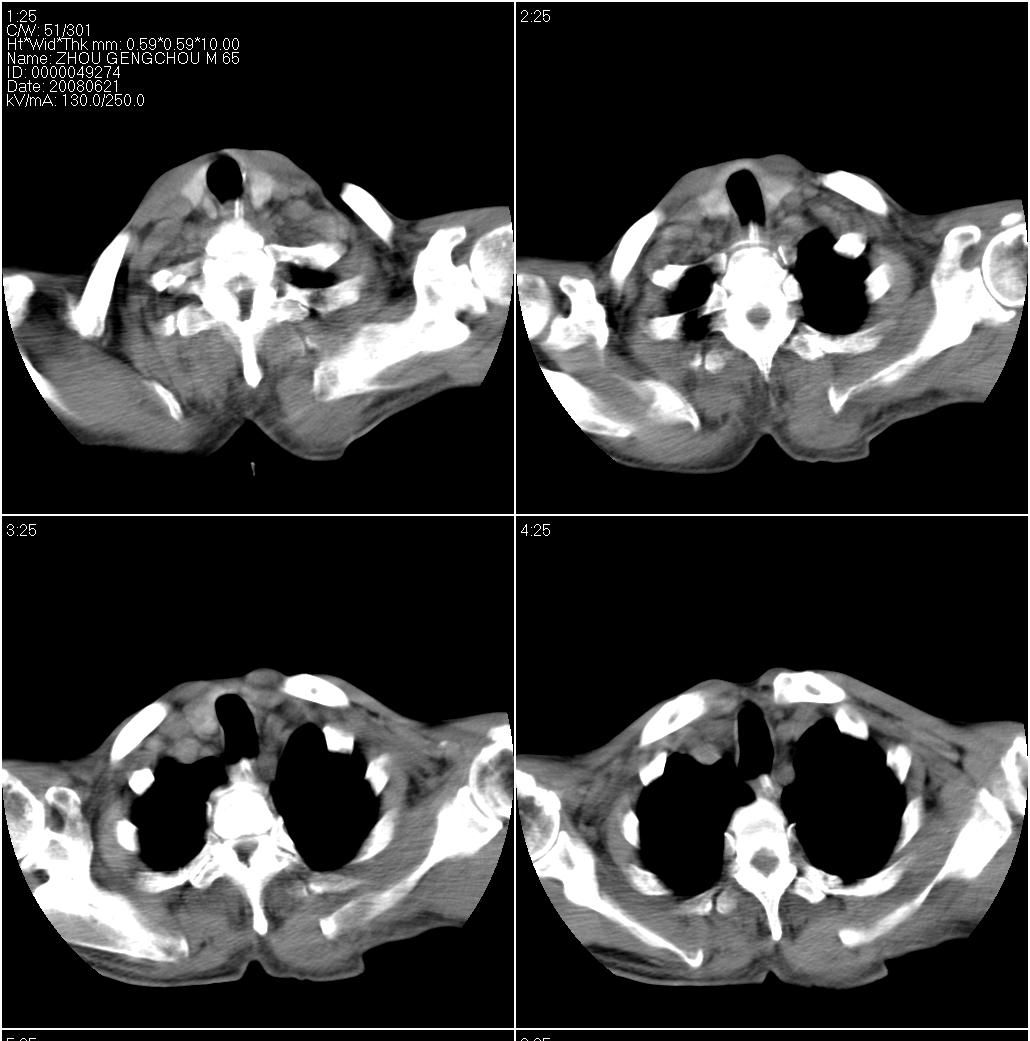

男性,65岁。因外伤来诊。该患者因脑外伤住院。以下是今天的dr和ct:

以下是一周前外伤时的dr:

右侧第七肋骨骨折伴肺挫伤

右侧第7肋骨腋段骨折并右肺挫伤;左侧膈疝并肺不张。

1 左下肺压迫性肺不张拌血胸

2 右侧肋骨骨折伴右肺挫裂伤